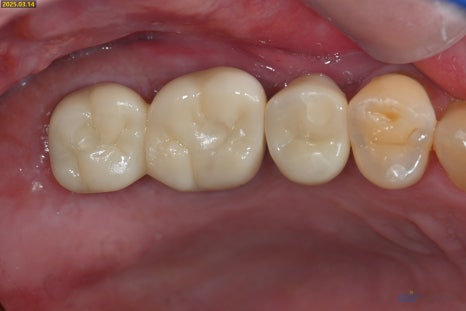

약 6개월 후 상악의 뼈가 충분히 단단해진 것을 확인하고

임플란트를 완성해드렸습니다

왼쪽 치료 전, 오른쪽 치료 후